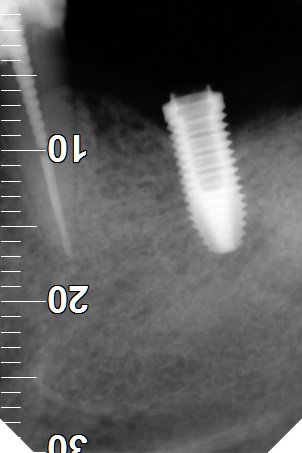

IDENTIFICAR IMPLANTES DEL MAXILAR SUPERIOR

Paciente acude a consulta para rehabilitarlos. La clínica donde se los colocó cerró y no puede localizarlos